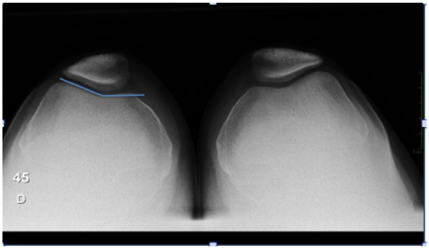

Knee radiograph evaluation (Figure 1 & 2) demonstrated a trochlear groove angle > 145º and type III patella according to the Wiberg classification as well as a crossing sign; there were no arthritic changes and no patella alta or baja; CT scan (Figure 3) showed femoral trochlea dysplasia, normal TT-TG, patella external translation and patella chondromalacia; MRI had the same findings as the CT and reported normal menisci and ligaments.

Figure 1 45º x-ray patellofemoral view (Merchant view) demonstrating trochlear groove angle > 145º and type III patella according to the Wiberg classification.